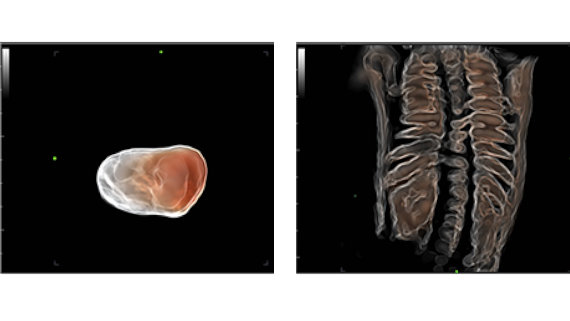

? Semplicit├Ā grazie all'ottimizzazione automatica dell'immagine - Smart Face

Con un semplice tocco, Smart Face consente di ottenere una visualizzazione ottimizzata rapida e intelligente del volto del feto. Il dispositivo ├© in grado di rimuovere immediatamente ostacoli come il cordone ombelicale, la placenta, l'utero e le estremit├Ā nei dati del volume ed elimina informazioni di disturbo, in modo da generare una visuale ottimale del volto fetale con maggiore semplicit├Ā.

? Precisione grazie all'acquisizione smart - Smart Planes CNS

Smart Planes CNS ├© uno strumento intuitivo che aumenta notevolmente l'accuratezza della scansione e garantisce un funzionamento completamente automatizzato che consente di ottenere una diagnosi accurata, un migliore rendimento e una minore dipendenza dall'utente. Con il semplice clic di un pulsante su un'immagine volumetrica 3D del cervello fetale, ├© possibile ottenere immediatamente e con precisione piani di scansione standard del sistema nervoso centrale (MSP, TCP, TTP e TVP) e una serie di misurazioni anatomiche correlate (BPD, HC, OFD, TCD, CM e LVW).